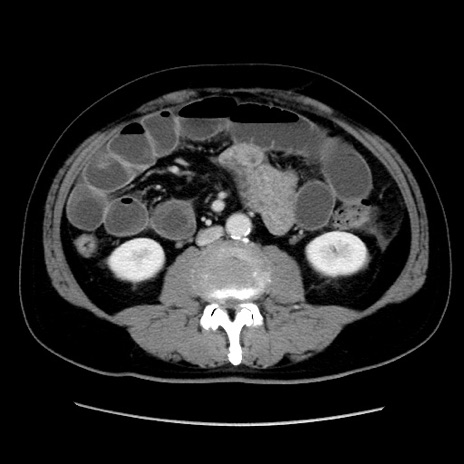

症例16(横断像)

【症例】 70歳代男性

【主訴】 腹痛、嘔吐

【現病歴】 約1ヶ月前より間欠的に腹痛と嘔吐あり、当院消化器内科を受診したところCTで多発する肝臓のLDAを指摘され、精査中であった。以降は消化器症状は安定していたが、2日前より嘔気と腹痛があり、同日より排便・排ガスが消失した。改善認めず、 本日、救急外来を受診した。

【既往歴】 大腸ポリープ切除後。

【身体所見】意識清明・会話良好、BT 36.3℃、BP 127/80mmHg、 P 80bpm、腹部:膨満あり、平坦・軟、上腹部正中および下腹部正中に圧痛あり、反跳痛なし、筋性防御なし。

【データ】WBC 7200、CRP 0.77